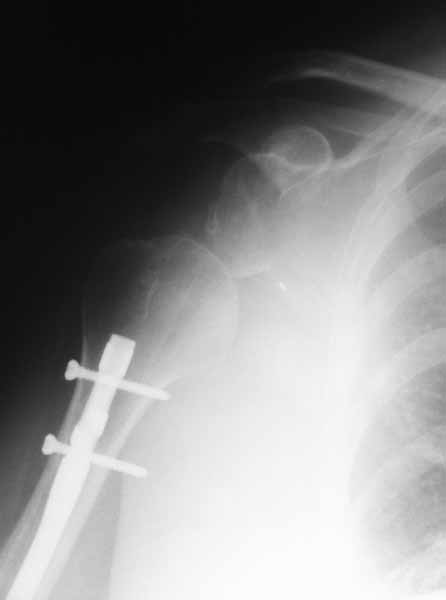

Re: Застарелый вывих головки плечевой кости

Плечевой сустав на сегодняший день спустя 10 мес. после травмы.